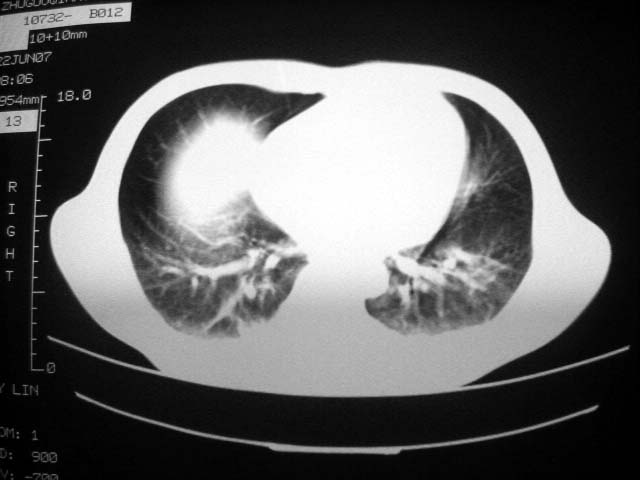

标题: CT7988D:近期图像 出乎意料!

从ct7988c 至今未用任何抗生素及抗痨药,维持保肝治疗。患者低热、咳血渐消失。

07年6月22号复查

前几次大家认为是转移癌,但此次复查病灶却明显吸收好转,不支持诊断。请大家讨论。[emb10]

患者现无咳嗽咳痰及咳血,肝功好转,血清白蛋白降低,球蛋白升高,白球比小于0.5.少量腹水。

回顾既往片,病变明显吸收,缩小,未经治疗,不支持肺转移瘤,可能为肺结节病或韦格氏肉芽肿

支持韦格氏肉芽肿

患者近期复查胸ct正常,轻度肝功异常,保肝、抗病毒(拉美夫叮)治疗中。